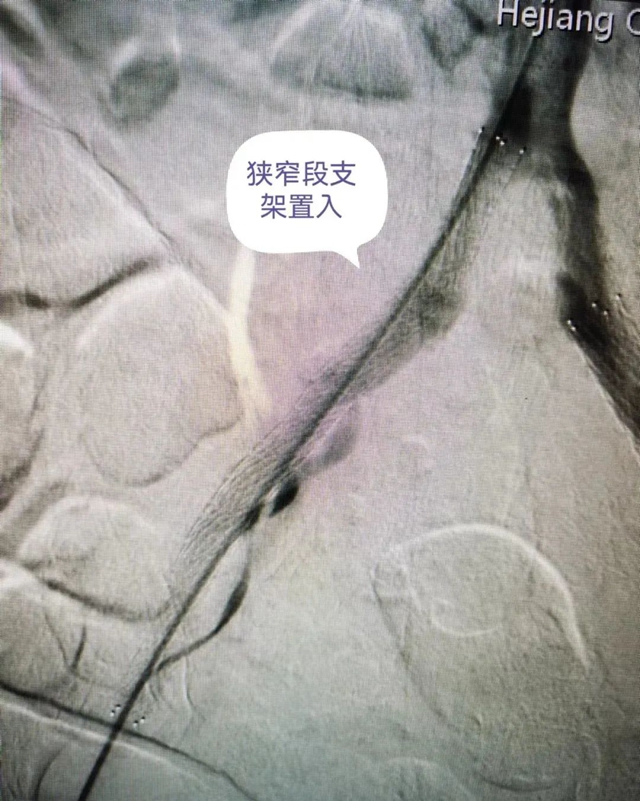

支架置入